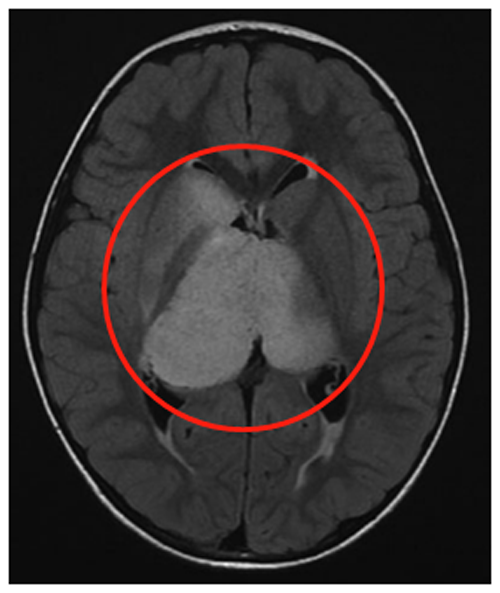

6岁男童临床表现为头痛、间歇性左上肢震颤。MRI(FLAIR序列)显示双侧丘脑肿瘤,右侧大于左侧,累及尾状核头部。脑室轻度增大,伴膈膜水肿和肿瘤内部囊肿。

治疗团队先行左额部内窥镜活检和鼻中隔造瘘术,后续行左枕脑室-腹腔分流术。组织病理诊断为WHO III级间变性星形细胞瘤,H3K27M、p53、BRAF V600E突变免疫阴性,MIB-1增殖指数达40%。

制定综合治疗方案:同步替莫唑胺(TMZ)和放射治疗(59.4Gy),后续完成12周期替莫唑胺治疗(累计剂量200mg/m²)。确诊后15个月影像学表现稳定,临床症状缓解,生活质量显著提升。